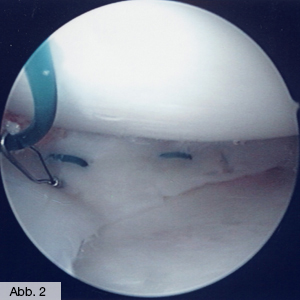

Im Gegensatz zu den verschleißbedingten Meniskusschäden des älteren Menschen ist es bei verletzungsbedingten Meniskusschäden des Sportlers oftmals möglich, den gerissenen Meniskus durch Naht zu heilen. Die Möglichkeit einer Meniskusnaht (Abb. 2) ist allerdings von der Ausdehnung des Schadens und der Rissform abhängig. In jedem Falle sollte aber bei jungen und sportlich aktiven Menschen der Erhalt des Meniskus wenn immer möglich angestrebt werden. Die Operation wird immer arthroskopisch durchgeführt: in einem ersten Schritt wird die Ausdehnung des Meniskusschadens klassifiziert. Dann erfolgt – wenn möglich – die Naht durch arthroskopische Nahttechniken oder durch spezielle Nahtanker.